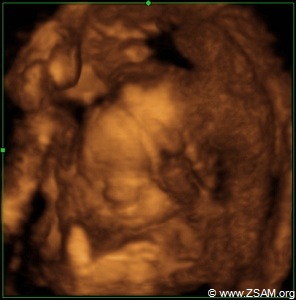

Baby-Nest. The best drugs are: Love and a baby, that is looking and smiling with its big eyes into yours. Grub eats laughing baby! Child offers soother to chancellor!